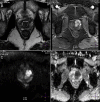

Diagnosis of prostate cancer (PCa) and adequate staging play a fundamental role for clinical and patient care. Despite major advances in biology and imaging, rectal examination and prostate-specific antigen (PSA) blood test remain the cornerstone for screening, and multiparametricmagnetic resonance imaging (mpMRI) for local staging. Recent advances in mpMRI lead to standardised interpretation and increased prescription by clinicians in order to improve detection of clinically significant PCa and select patients requiring targeted biopsies. However its indication remains controversial in biopsy-naïve patients. Nuclear medicine is also in a continuous evolution and utilisation of new radiopharmaceutical agent like choline or 68gallium with computed tomography or magnetic resonance imaging has led to the improvement in the detection of lymph nodes, distant metastases and prostate recurrence. Considering this very heterogneneous disease, combined utilisation of these tools will help clinicians and patients in choosing the most appropriate and personalised treatment.